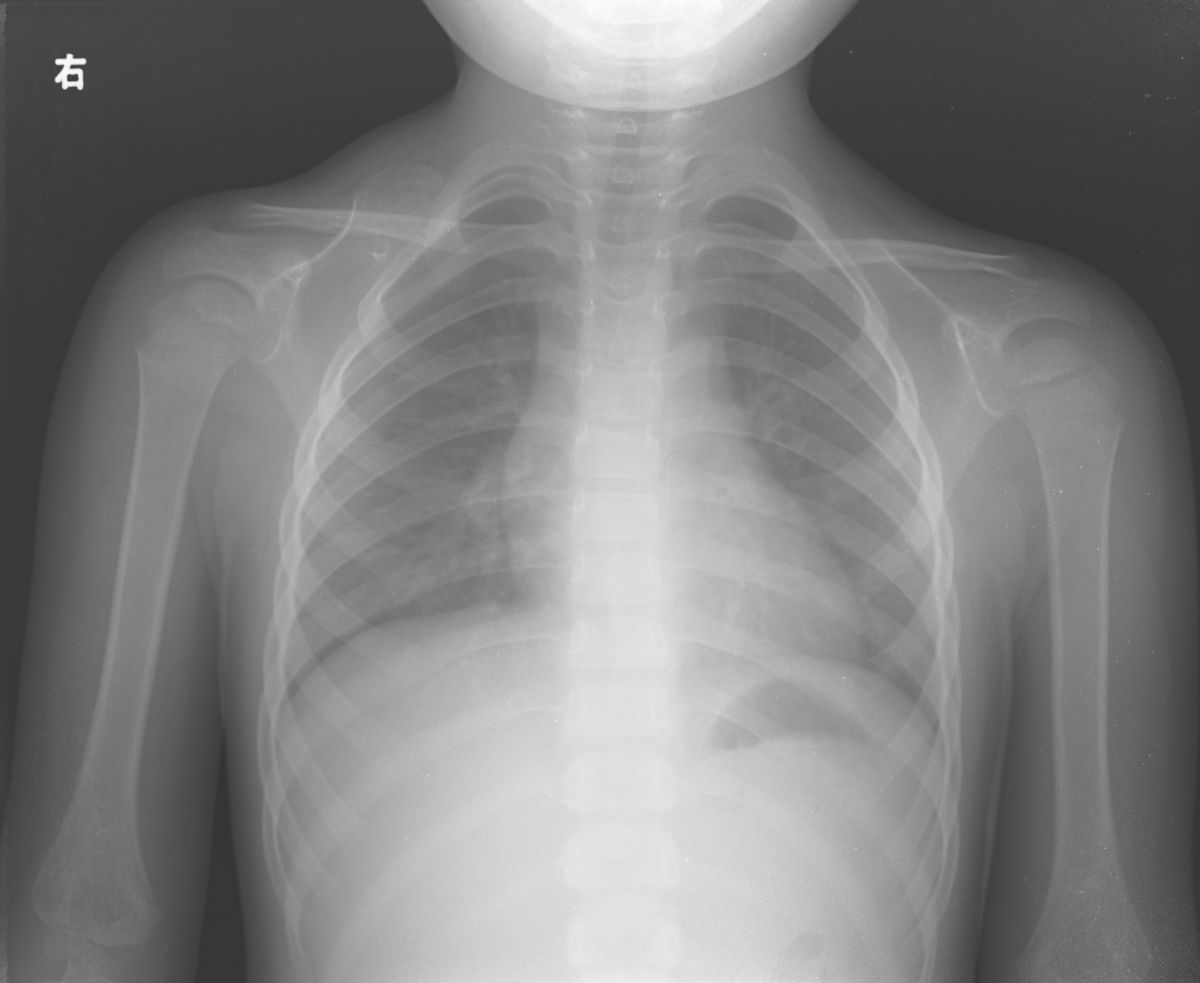

以下是引用杀毒软件在2009-7-2 18:53:00的发言:[br]先考虑---先天性高位肩胛症,不排除-----右肩胛骨骨软骨瘤或骨质肥大畸形。

以下是引用dr.yang在2009-7-2 23:12:00的发言:[br]右肩胛骨骨软骨瘤或骨质肥大畸形。不象先天性高位肩胛症